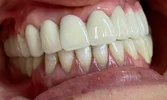

Klinik çalışmalarını İmplant ve Estetik diş hekimliği uygulamaları konusunda yoğunlaştırmıştır.

Zirkonyum uygulamalar

Porselen uygulamaları

Laminate veneer